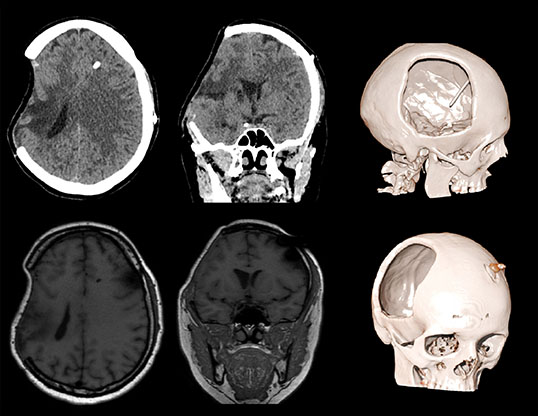

Визуализируется обширная инвагинация кожного лоскута в полость дефекта, смещение срединных структур влево, сдавление САП правого полушария и сглаженность борозд. Причиной данного состояния явилась гиперфункция шунта.

Данному пациенту была произведена краниопластика дефекта черепа, коррекция программируемого клапана давления. Пациент выписан на третьи сутки в удовлетворительном состоянии с полным регрессом неврологической симптоматики.